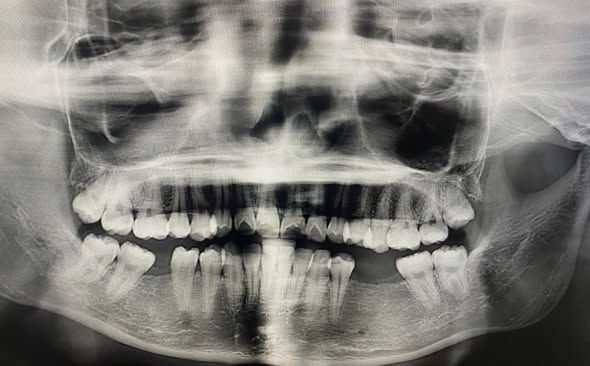

Bệnh nhân nữ 20 tuổi, bị mất 3 răng r35,36,45. Sau khi tiến hành thăm khám, chụp phim X-quang đã được đội ngũ các y bác sĩ lên kế hoạch điều trị và cấy ghép implant để thay thế những chiếc răng mất, giúp bệnh nhân đảm bảo được hiệu quả ăn nhai tuyệt đối và thẩm mỹ, tránh các biến chứng nặng nề do mất răng gây ra kịp thời